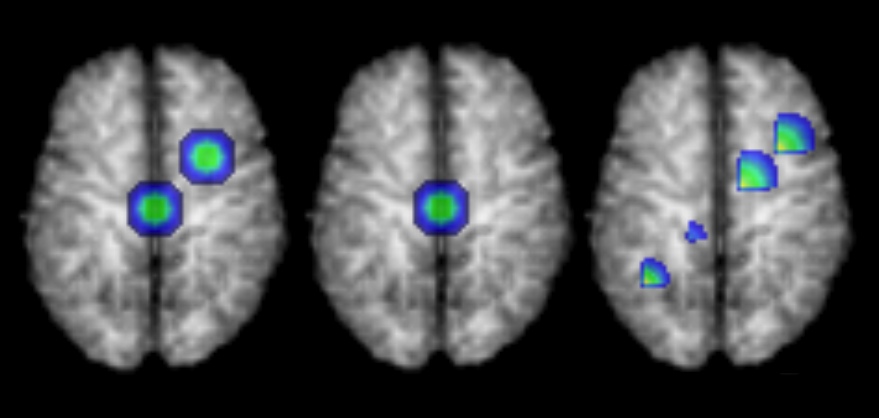

For scenarios (S.1) - (S.4), the elements of isubscript𝑖\mathcal{E}_{i} were independently generated from a N(0,702)N0superscript702\mbox{N}(0,70^{2}) generator. For scenarios (S.5) - (S.8), the elements of i=(i(g))subscript𝑖subscript𝑖𝑔\mathcal{E}_{i}=(\mathcal{E}_{i}(g)) were generated to reflect a short range spatial dependency. Specifically, let i(g)=gg11Ei(g)/mgsubscript𝑖𝑔subscriptsubscriptdelimited-∥∥superscript𝑔𝑔11subscriptsuperscript𝐸𝑖superscript𝑔subscript𝑚𝑔\mathcal{E}_{i}(g)=\sum_{\lVert g^{\prime}-g\rVert_{1}\leq 1}{E}^{*}_{i}(g^{\prime})/m_{g}, where g𝑔g is a voxel in the three-dimensional space, Ei(g)N(0,702)similar-tosubscriptsuperscript𝐸𝑖𝑔N0superscript702{E}^{*}_{i}(g)\sim\mbox{N}(0,70^{2}), .1\lVert.\rVert_{1} is the L1subscript𝐿1L_{1} norm of a vector, and mgsubscript𝑚𝑔m_{g} is the number of locations in the set {gg11}subscriptdelimited-∥∥superscript𝑔𝑔11\{\lVert g^{\prime}-g\rVert_{1}\leq 1\}. Figure 3 shows the 3D rendering of 𝒳0subscript𝒳0\mathcal{X}_{0} overlaid on the template 𝒢0subscript𝒢0\mathcal{G}_{0}.

Refer to caption

Figure 3: The 3D rendering of signal 𝒳0subscript𝒳0\mathcal{X}_{0} overlaid on the template 𝒢0subscript𝒢0\mathcal{G}_{0} for scenarios 1, 2, and 3, respectively. 𝒳0subscript𝒳0\mathcal{X}_{0} is equivalent for scenarios 3 and 4.